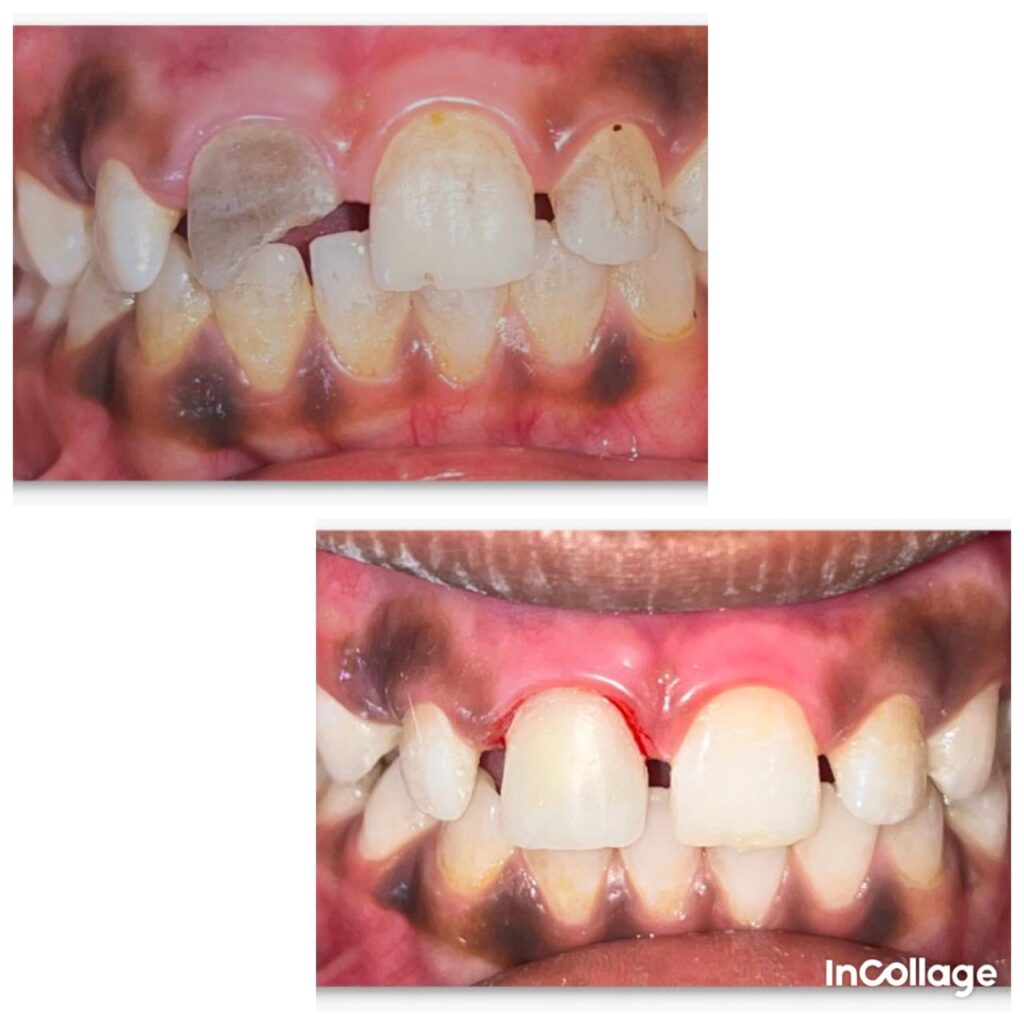

- Aesthetic Composite Restorations

She is proficient in restorative procedures such as post and core as well as aesthetic composite restorations, ensuring both functional and aesthetic rehabilitation. Dr. Pangire emphasizes minimal chair time, painless treatment experiences, and consistent follow-ups to maintain high standards of patient care. Known for her clear communication and effective chair-side case discussions, she contributes positively to patient trust and treatment acceptance.

Single Setting Root Canal Treatement